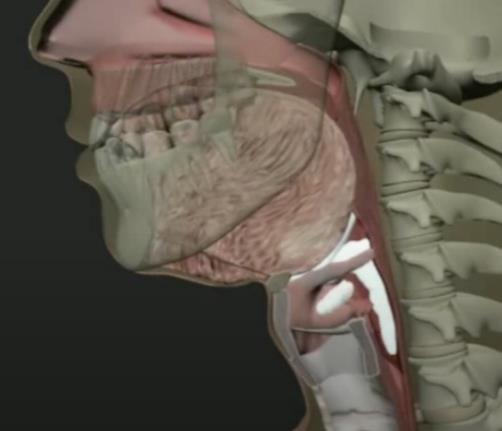

Oral phase

Pharyngeal Phase

pharyngeal/e sophageal phases

Esophageal phase

Anatomical & Functional Differences in Swallowing: Children vs. Adults